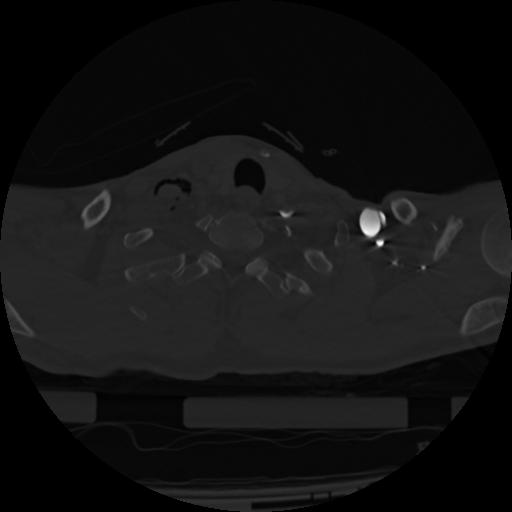

22 ANGIO,CE,Vol,0.5,ANGIO,,